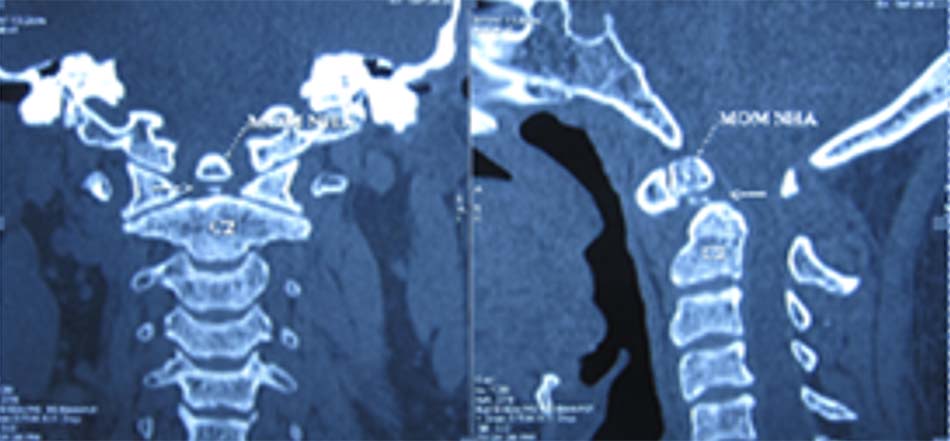

Spitzer và cộng sự đã mô tả mất vững khớp chẩm – đội và thiểu sản đốt đội trong hội chứng Down [12]. Phân loại dị tật mỏm nha chia ra:

- Không có mỏm nha: là dị tật mỏm nha không phát triển, trên Xquang thường quy không có mỏm nha.

Hình 1.35. Hình ảnh Xquang không có mỏm nha. - Thiểu sản mỏm nha: mỏm nha phát triển bán phần, có hình dạng khác nhau có thể là 1 mẩu ngắn hoặc có thể có kích thước gần như bình thường.

Hình 1.36. Thiểu sản mỏm nha trên Xquang - Khớp giả mỏm nha: Mỏm nha được chia làm 2 đoạn, trong đó có một đoạn tách rời.

Hình 1.37. Mất vững C1-C2, khớp giả mỏm nha trên Xquang thường quy

Hình 1.38. Khớp giả mỏm nha trên cắt lớp vi tính (hội chứng Down).